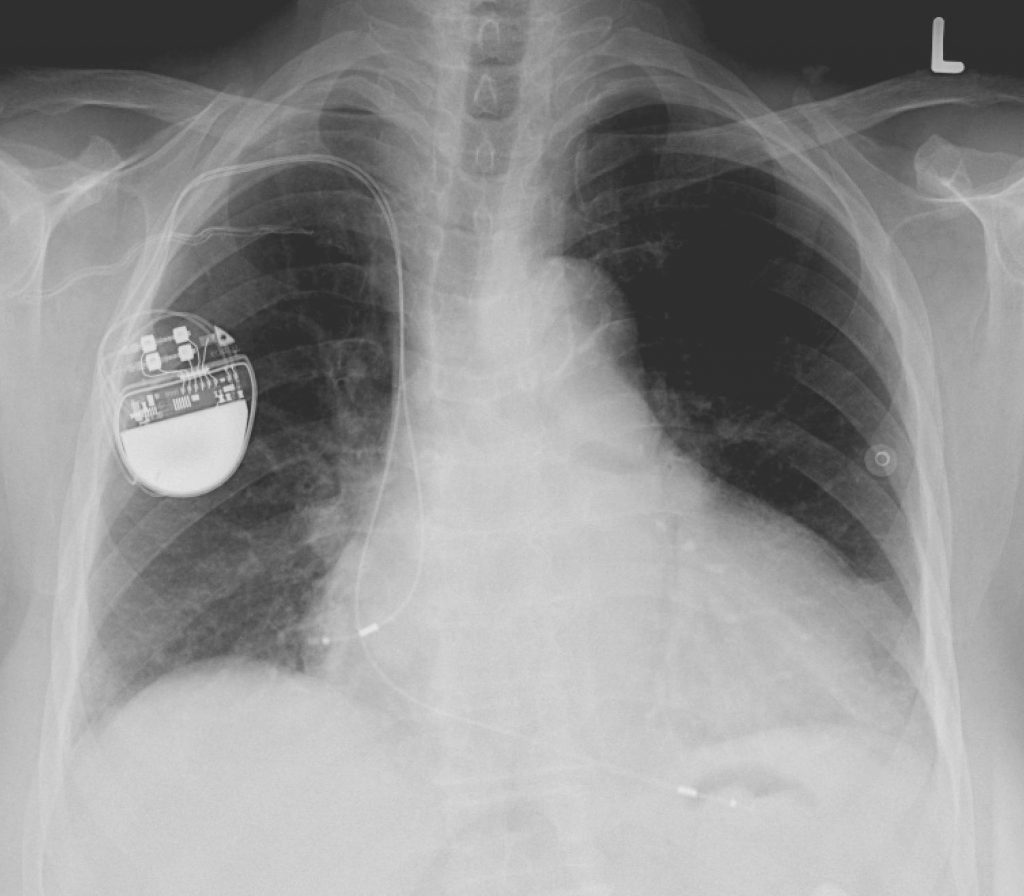

13. Pacemaker

There was a time when, if your heart started acting funny, you either got hooked up to a tv-sized box or died. Luckily, in the 1950s, Wilson Greatbatch screwed up his prototype for recording heart sounds when he grabbed a 1 mega-ohm resistor instead of a 10,000 ohm resistor out of his box of resistors and plunked it down on his circuit board. Greatbatch realized he could use the precise current to regulate a pulse and remove the need for the previous cumbersome apparatus. While this pretty much ruined his original project, it did revolutionize the pacemaker.